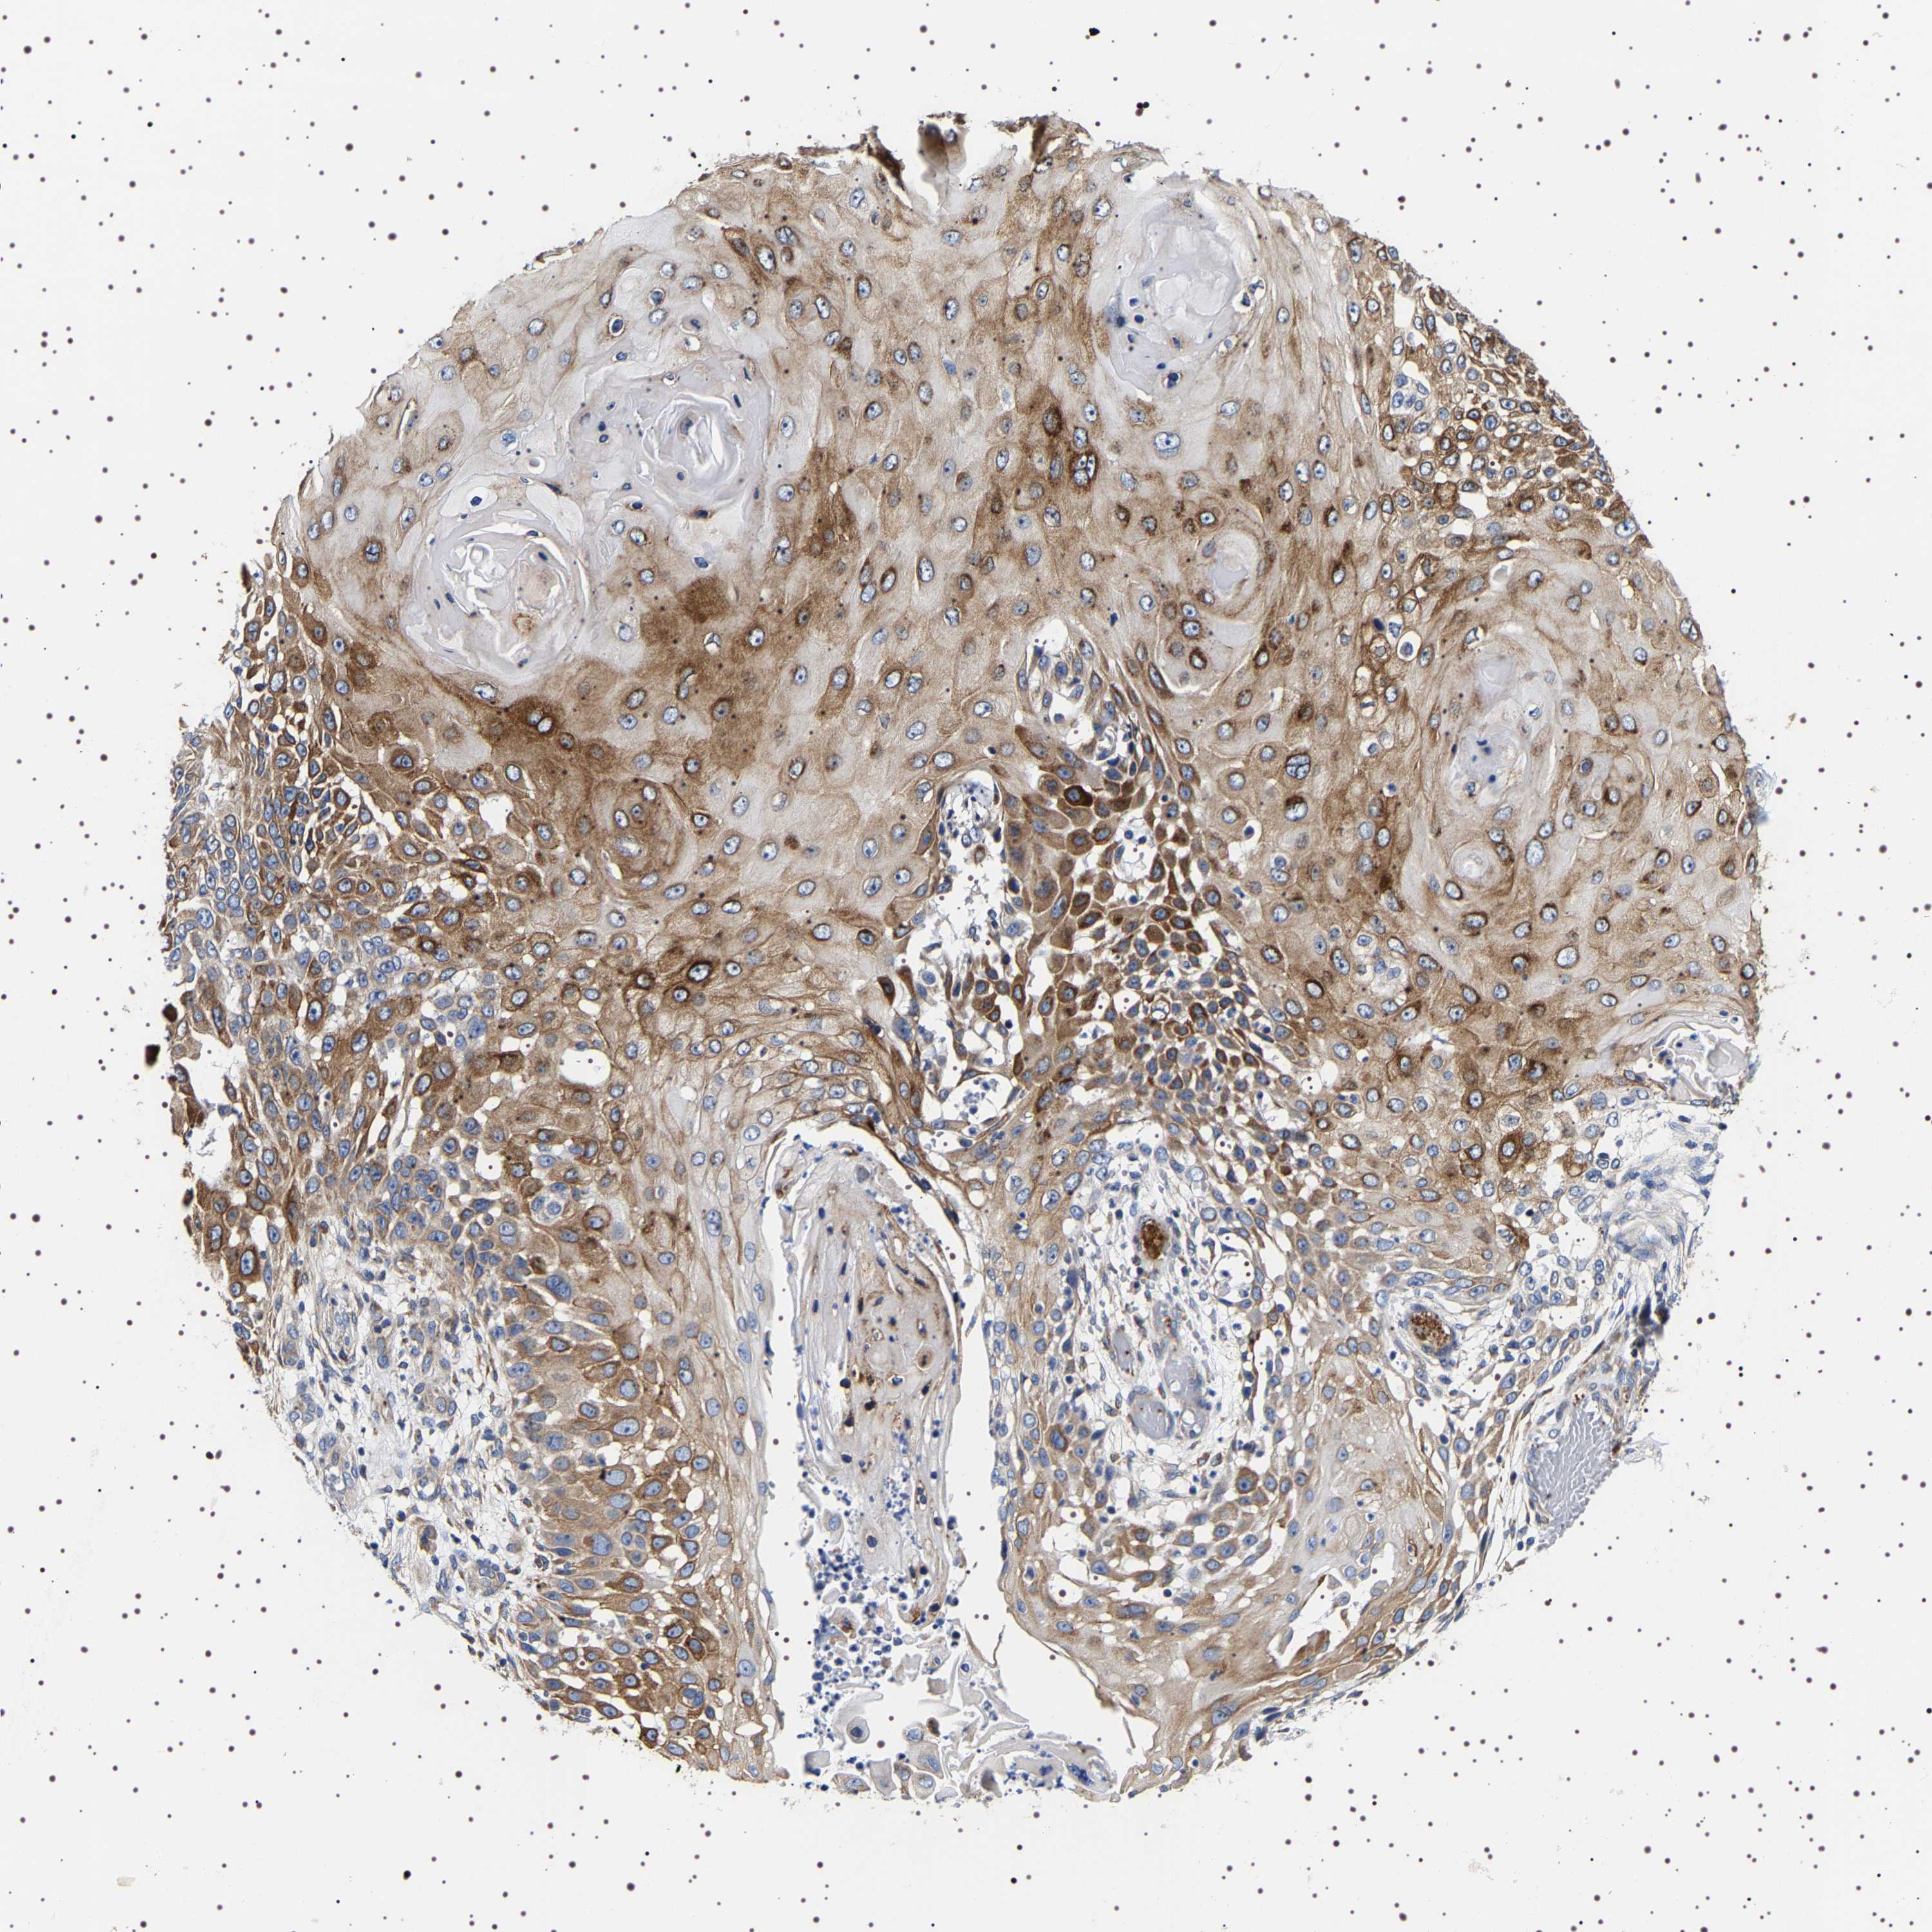

SKIN CANCER - Protein expressioni

A mouse-over function shows sample information and annotation data. Click on an image to view it in a full screen mode. Samples can be filtered based on level of antibody staining by selecting one or several of the following categories: high, medium, low and not detected. The assay and annotation is described here.

Each image is clickable and will lead to virtual microscopy that enables deeper exploration of all samples and also displays staining intensity scores, fraction scores and subcellular localization as well as patient and tissue information for each sample.

Antibody HPA018038

Staining

High

Medium

Low

Not detected

Intensity

Strong

Moderate

Weak

Negative

Quantity

>75%

75%-25%

<25%

None

Location

Nuclear

Cytoplasmic/membranous

Cytoplasmic/membranous,nuclear

Squamous cell carcinoma in situ, NOS

Squamous cell carcinoma, NOS

Squamous cell carcinoma, metastatic, NOS

Basal cell carcinoma